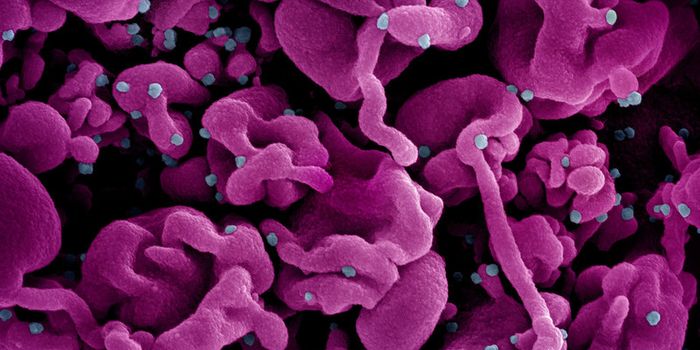

MAY 23, 2024MicrobiologyWhen human immunodeficiency virus (HIV) emerged and was identified as the cause of acquired immunodeficiency syndrome (A ...